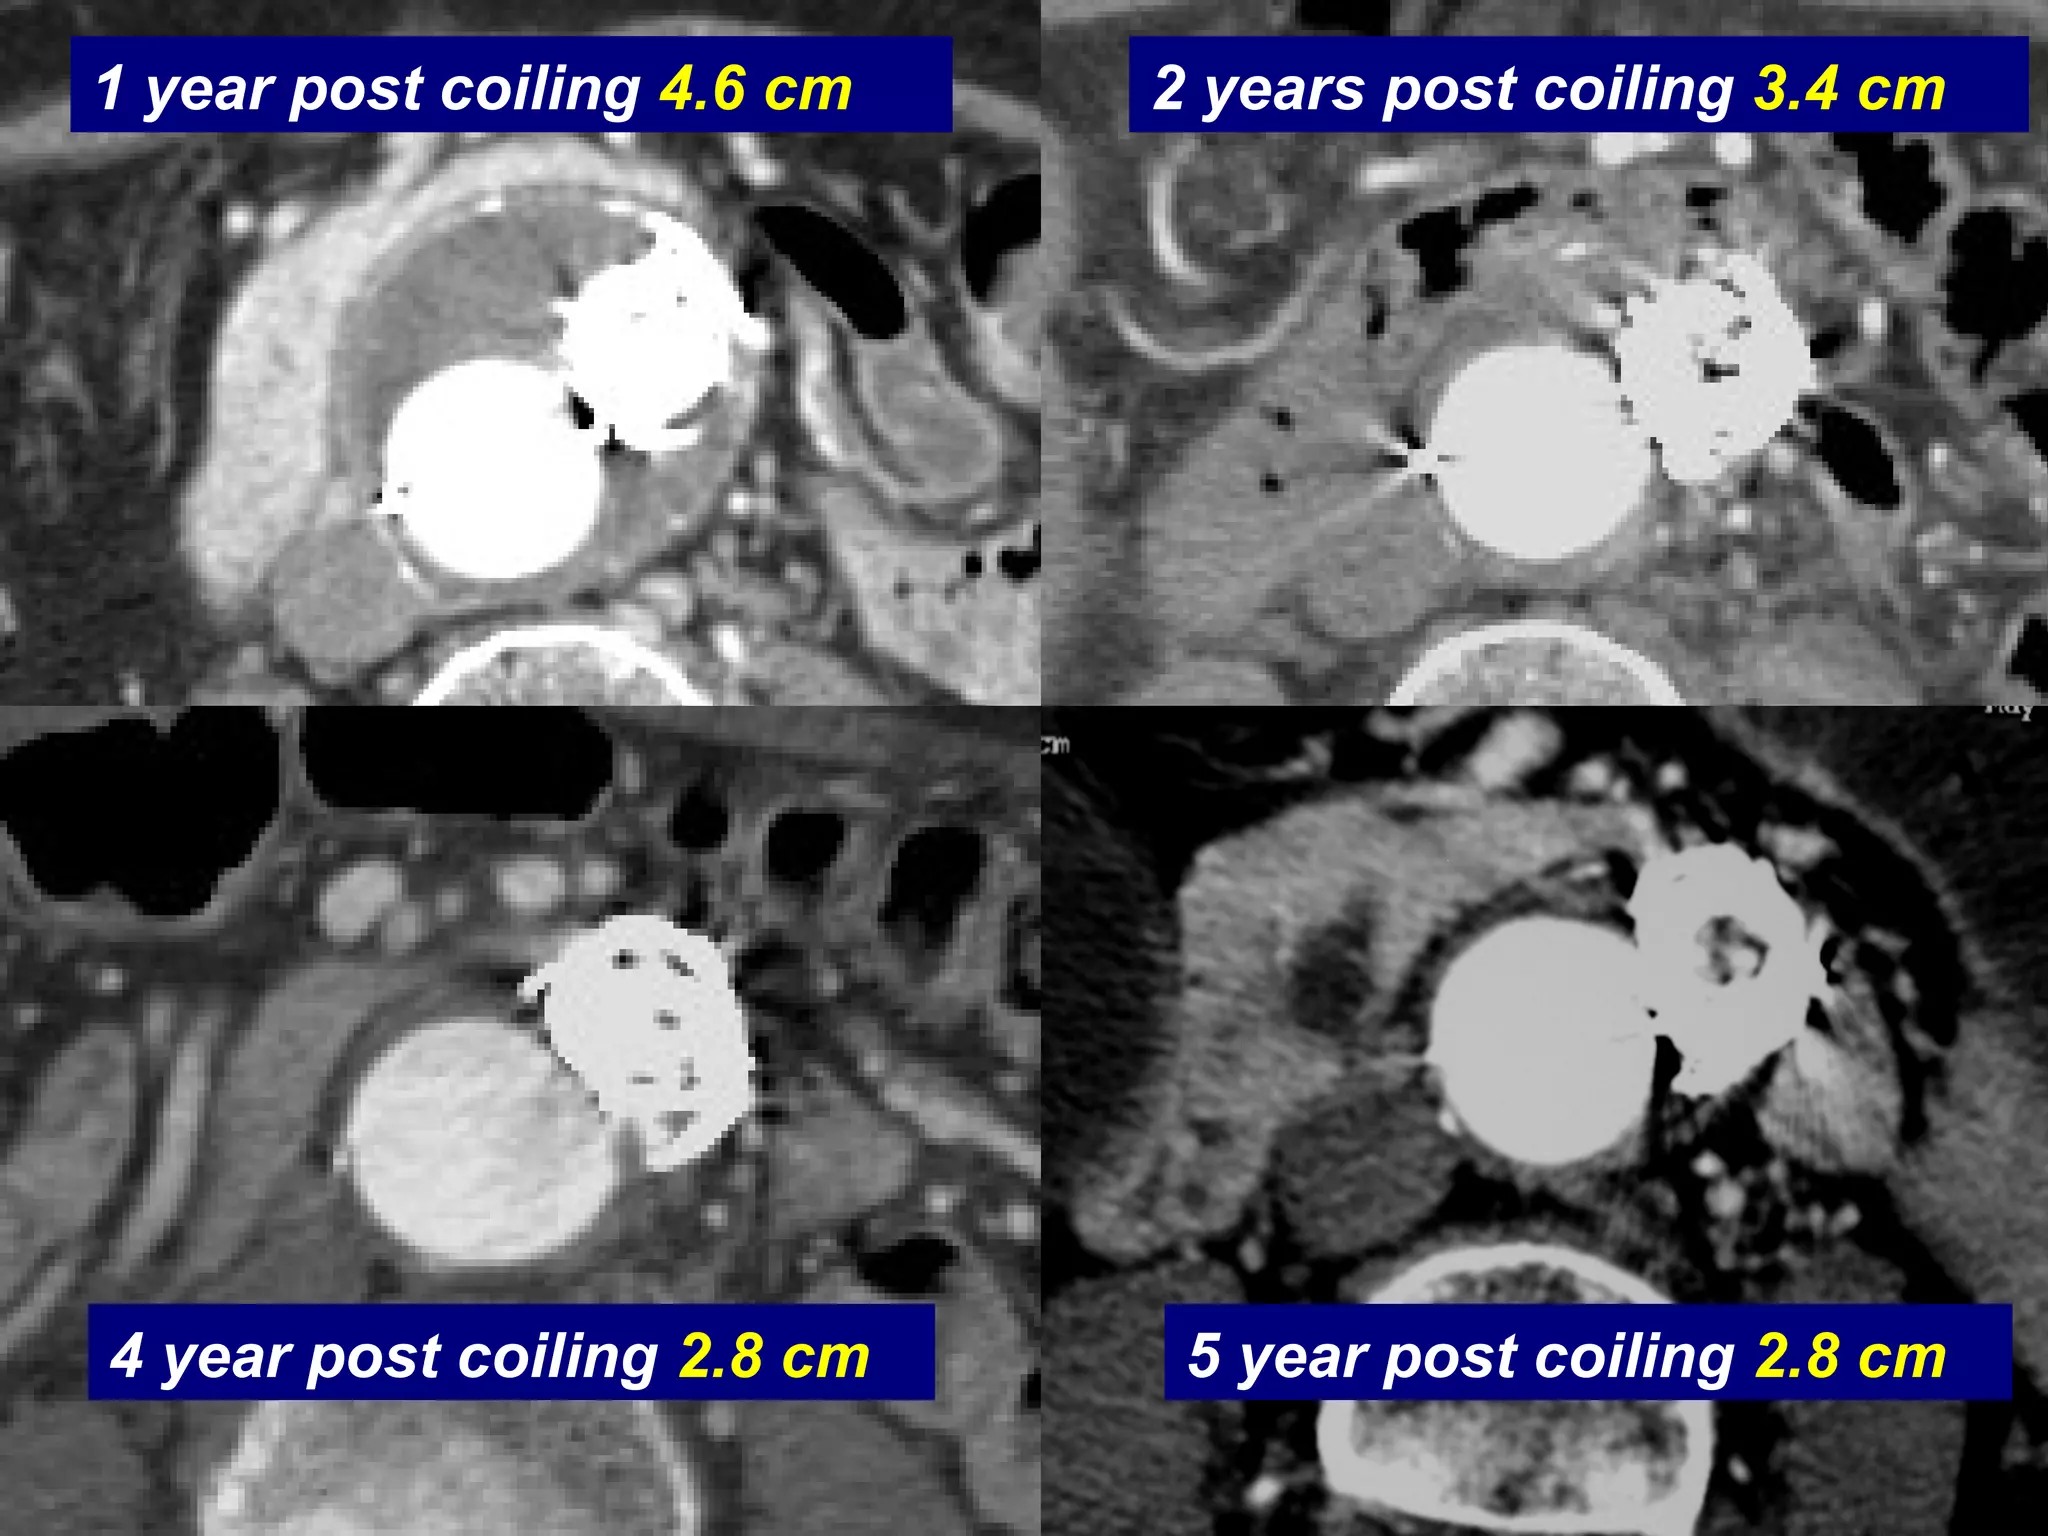

Coiling of Distal Type I

6 months post Tube Ancure

Distal Type I

Graft

Endoleak

Coils

1 Month Post Coiling 5.8 cm

1 year post coiling 4.6 cm 2 years post coiling 3.4 cm

5 year post coiling 2.8 cm4 year post coiling 2.8 cm